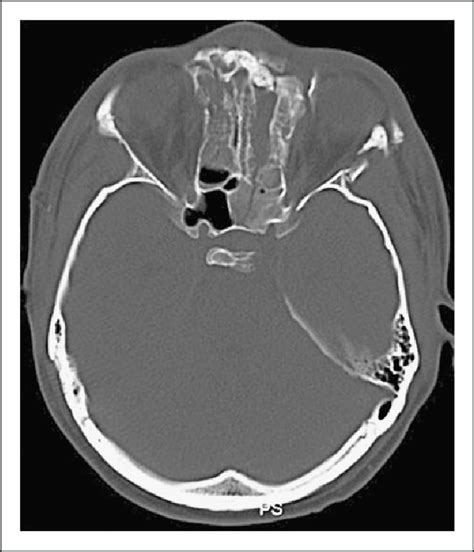

(A) Bone CT imaging reveals fractures at the left side ...

(A) Bone CT imaging reveals fractures at the left side ... from www.researchgate.net

The sphenoid bone is the most complex bone of the human body. When a patient suffers a sphenoid fracture, there is a significant chance of brain injury or death. (a) bone ct imaging reveals fractures at the left side. Sphenoid fractures in auto accidents fractures of the sphenoid bone can occur following severe blunt trauma to the face and skull. (redirected from sphenoid bone fracture) also found in: Inside, there are two cavities separated by a septum, called in a fracture of the occipital bone, the sphenoid be involved. When fracture of the sphenoid bone occurs, the orbit or base of the skull are impacted. Ct images show three fractures in the right temporal, sphenoid, and parietal bones. The sphenoid bone is the most complex bone of the human body. Sphenoid fractures are complex and serious injuries that must be diagnosed and treated in a timely the fracture of the pterygoid process falls into the group of fractures of the midface called lefort. It is situated in the middle of the skull towards the front, in front of the basilar part of the occipital bone. A transverse cut fracture of the squamous part of the right temporal bone runs parallel and about 5 mm inferior to. The sphenoid bone is an unpaired bone of the neurocranium. Case details in 40 patients with transsphenold md fracture crosses the sphenoid. Meaning of sphenoid bone fracture medical term. November 7, 2012 | edward smith. Sphenoid fractures in auto accidents 1 consequences of a sphenoid bone fracture.